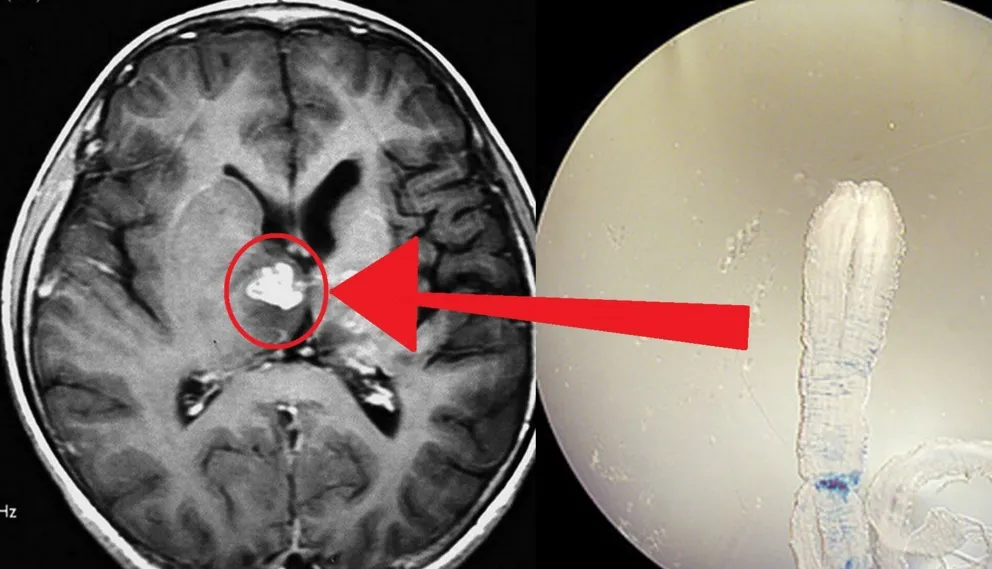

In CaliforniaHa mal di testa e va al pronto soccorso. I medici: hai ancora trenta minuti di vita15 febbraio 2020